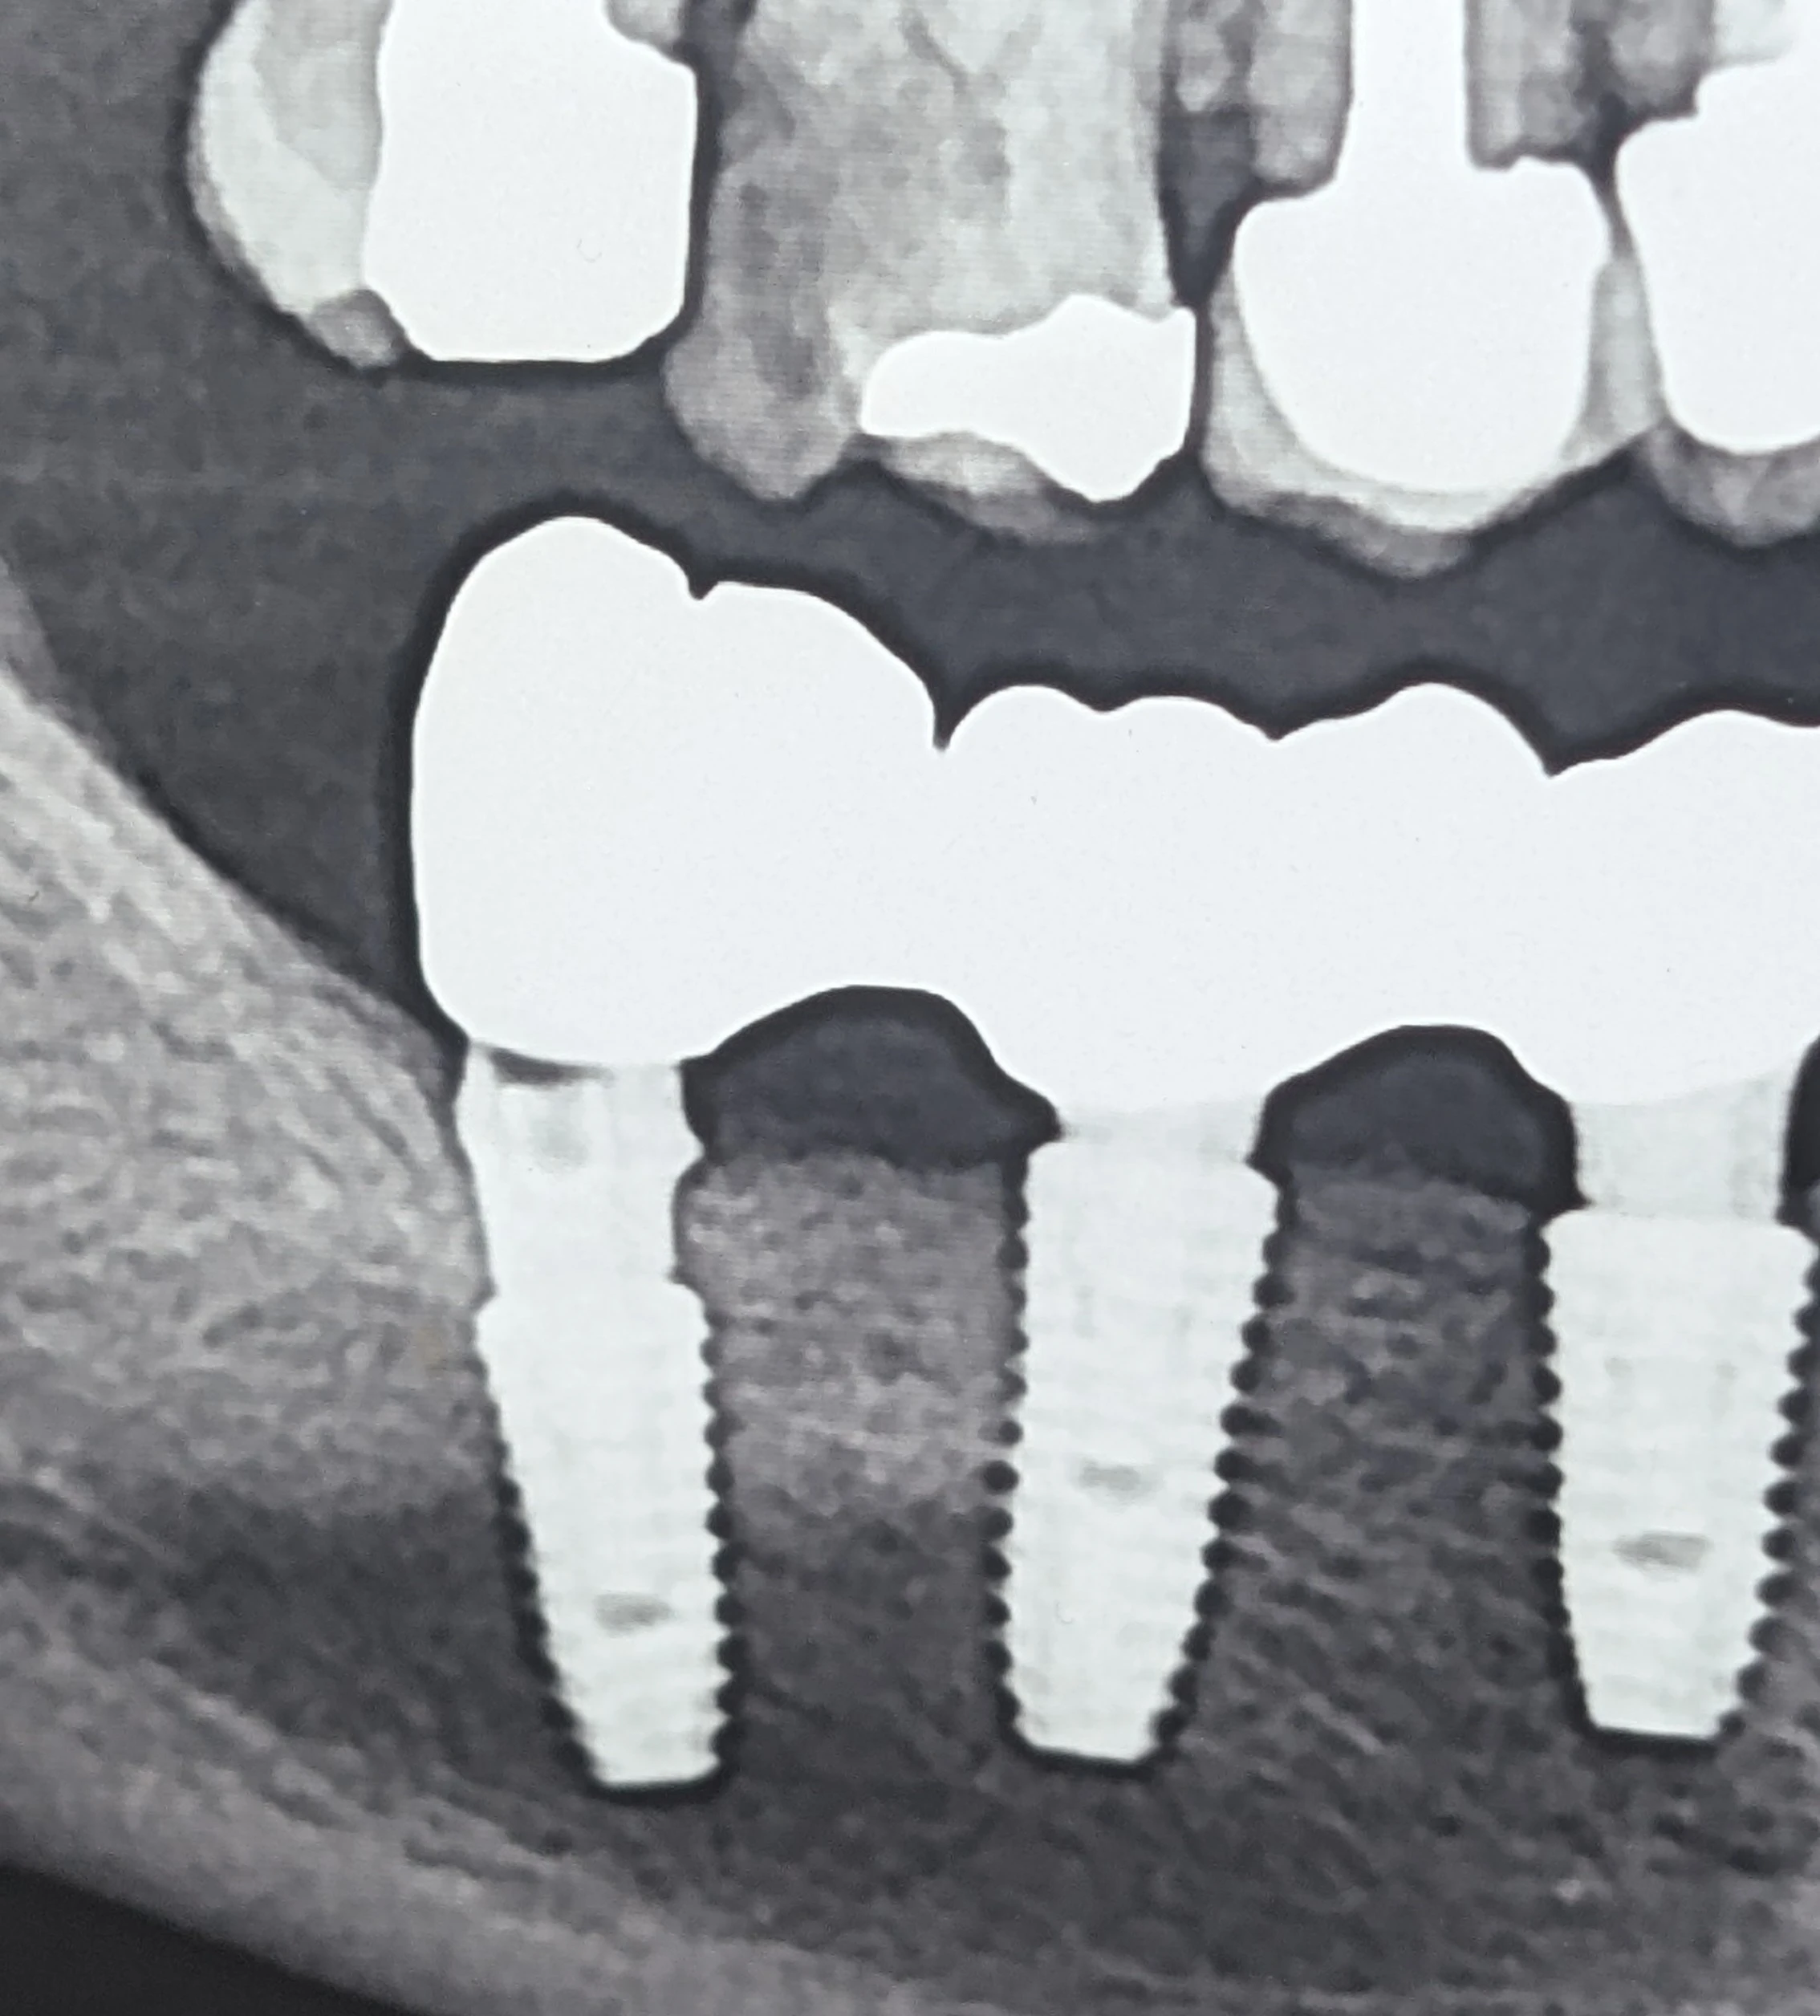

در یک مراجعه، بیمار با شکست در ناحیه جوینت بین واحدهای ۶ و ۷ مراجعه کرد. بررسی تصاویر پیش از شکست نشان داد که روکش واحد ۷ به‌طور کامل روی اباتمنت ننشسته بوده است.

پیامد این خطاها می‌تواند این باشد که سیستم طراحی، عملاً با یک مرجع اشتباه کار کند؛ برای مثال، تطابق با Scan Body کوتاه به‌جای نوع بلند و در نتیجه ساخت اباتمنتی با ارتفاع یا هندسه نامتناسب.

در رستوریشن‌های اسپلینت، گاهی عدم نشستن کامل یک واحد می‌تواند در مرحله سمان کردن کمتر واضح باشد؛ چون سازه به شکل یکپارچه نیرو و تماس‌ها را توزیع می‌کند و خطای یک واحد ممکن است در نگاه اول «ماسکه» شود.

اگر روکش عملاً ساپورت مؤثر از سمت اباتمنت نداشته باشد، تمرکز تنش در ناحیه کانکتور افزایش پیدا می‌کند و شکست از ناحیه جوینت می‌تواند رخ دهد.